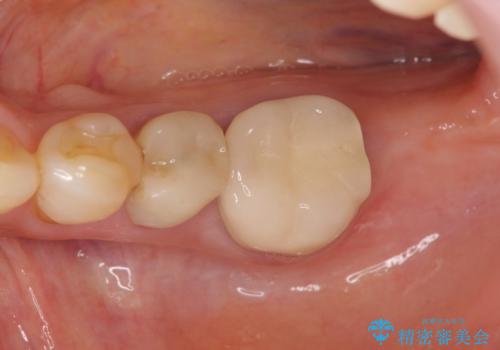

親知らずの移植 4年半経過症例 70代女性

- 親知らずの移植治療から4年半経過した患者様です。

移植した親知らずは全く問題ないそうで、「まるで自分の歯のようです。本当にすごい技術ですね。」とおっしゃって下さいました。

歯肉の腫脹や退縮、動揺も認められませんでした。

- ¥250,000 (自家歯牙移植、根管治療、仮歯、土台、被せ物)費用は治療当時の料金となります